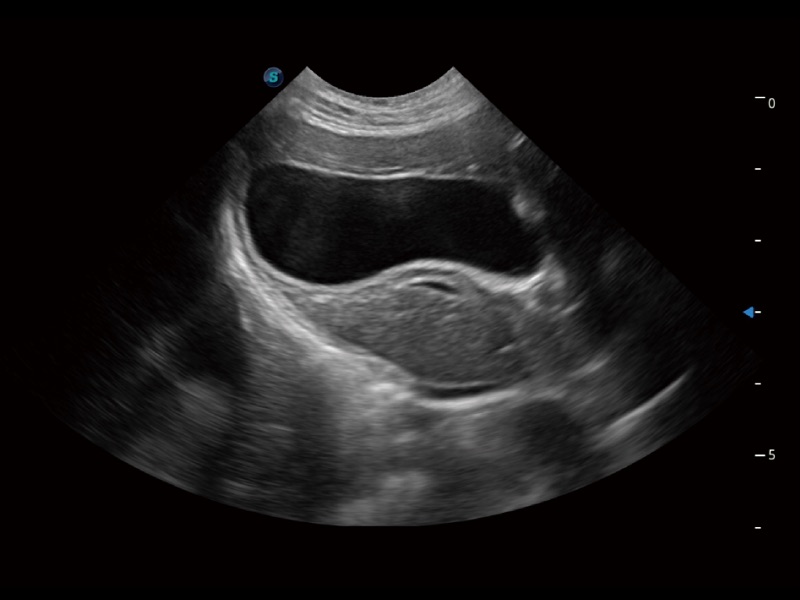

• Auto Bladder 膀胱自动测量

一键自动识别膀胱壁及自动测量膀胱容积,不受膀胱形状和大小的限制,帮助医生快速精准获得测量的数据。

(犬)肾脏显微血流

(猫)胆囊

(猫)肺动脉血流频谱

(犬)左室长轴血流

(犬)髂动脉血流

(犬)四腔心

(犬)胎儿主动脉弓立体血流

(犬)肝脏

(犬)四腔心MQA